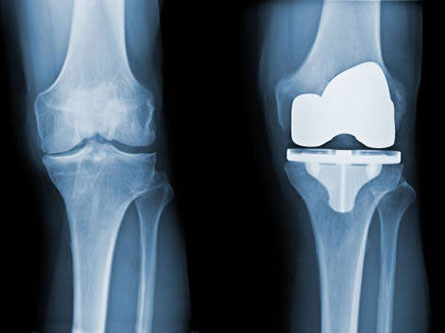

An orthopaedic surgeon shares guidance about how to decide whether knee replacement surgery is the right choice for you, as well as what the procedure and recovery involve.